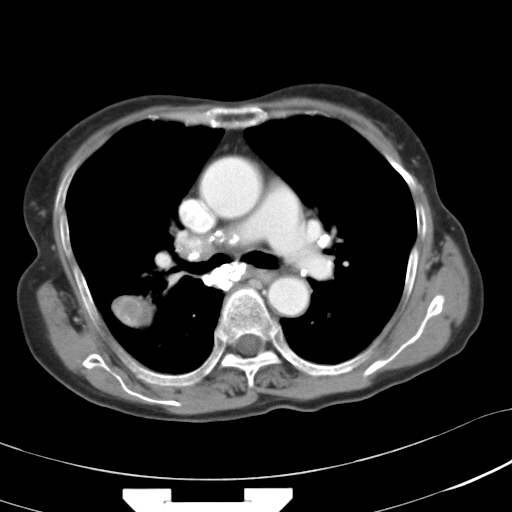

以下是引用hhcckk在2007-3-2 14:51:00的发言:[br]考虑结核球可能性大,依据[br]1病灶在下叶背段,结核的好发部位[br]2病灶内有大量的钙化,纵隔内有大量的淋巴结钙化[br]3重要的是半年前与现在相比无变化,假如是肿瘤的话不会这么‘善良’[br]4病灶周围卫星灶不明显,病灶有毛刺,胸膜凹陷,肿瘤不能完全排除,有条件的话最好做个活检

以下是引用liuyue在2007-3-2 17:15:00的发言:[br]1位置:右上叶后段[br]2性质:大分叶、粗长毛刺、条状斑片状钙化、纵隔多发淋巴结钙化,无强化,故考虑:肺结核灶(陈旧)